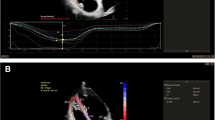

In echocardiography, data acquisition was performed by one of the expert sonographers using an EPICcv (Philips Medical Systems, Andover, MA, USA), equipped with a 5-MHz transducer, according to the established guidelines [10,11,12,13,14,15]. Echocardiography was generally performed without acute smoking exposure. Echocardiographically measured and derived variables were determined as follows: left ventricular mass (LVM) was calculated from left ventricular (LV) chamber size and wall thickness dimensions; 2-dimentional LVEF was computed from LV end-diastolic and end-systolic volumes which were calculated according to the bi-plane disk summation method in apical four- and two-chamber views; pulsed-wave Doppler was performed with the sample volume placed at the level of the mitral leaflet tips to obtain peak early (E) and late (A) diastolic transmitral inflow velocities and E-wave deceleration time; and tissue Doppler was performed to acquire mitral early (e′) and late (a′) diastolic annular velocities on the lateral side of the wall. To assess LV diastolic function, we used E/A ratio and E/e′ ratio. Right ventricular (RV) end-diastolic area was measured from an RV-focused apical four-chamber view. Right ventricular fractional area change (RVFAC), tricuspid annular plane systolic excursion (TAPSE), and RV peak systolic tissue Doppler velocity captured different dimensions of RV systolic function. RVFAC was obtained by tracing the RV endocardium from the annulus, along the free wall to the apex, back to the apex, then along the interventricular septum. To evaluate the RV diastolic function, tissue Doppler parameters were used: early diastolic peak velocity (e′t), late diastolic peak velocity (a′t) of the tricuspid annulus, and its ratio (e′t/a′t). Strain analyses were performed using a semi-automated speckle tracking technique (aCMQ, QLAB Cardiac Analysis, Philips Medical Systems, Andover, MA, USA). Three apical views were used to obtain an average global peak systolic longitudinal strain (GLS) with systole (Additional file 1: Figure 1).

Additional file 1: Figure 1

. A representative of strain analyses using a semi-automated speckle tracking technique. The three apical views were used to obtain an average global peak systolic longitudinal strain with systole. Figures a, b and c are the apical long axis, 2-, 3- and 4-chamber views, respectively. Figure d shows the Bull’s eye plot of left ventricular global longitudinal strain assessed by speckle tracking technique.